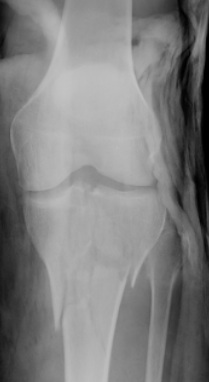

Proximal Tibia

Structures at risk

- CPN

- popliteal artery and tibial nerve

- saphenous nerve

Wires Proximal to TT

- safe arco degrees

- 3 wires

- one wire anterior to fibular head angled anteriorly

- one wire through fibular head straight across posterior tibia

- one wire through medial posterior tibia angled anteriorly

- creates a triangle of bone between wires

- always 10 - 15 mm distal to joint line to avoid proximal joint capsule

- can supplement one wire with two half pins below (HA coated) in the medial cortex

Wires Distal to TT

- safe arc 140o

- not safe to go through fibula

- direct wire transversely

Distal Tibia

- SPN

- DPN and anterior tibial artery

- posterior tibial artery and tibial nerve

Wires

- one wire through fibula head angled anteriorly

- one through posterior medial tibia, angled anteriorly

- one straight across

- again supplement with half pins above and below